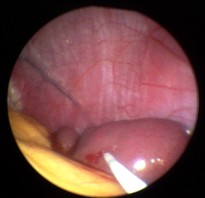

Milzbiopsie bei Sarkoidose